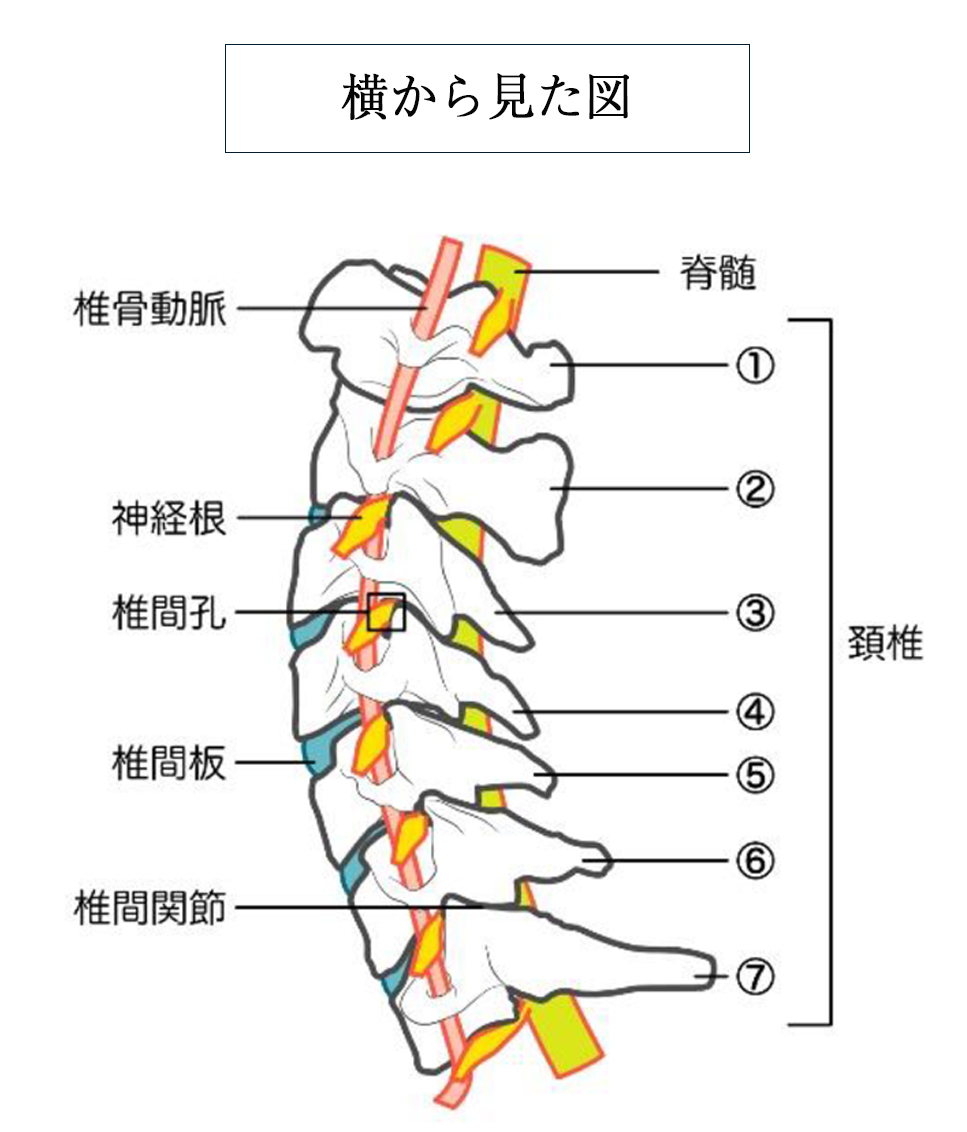

また首は7個の椎骨からなる頸椎と、板状筋、胸鎖乳突筋、僧帽筋などの筋肉で頭を支えています。

さらに椎骨と椎骨との間には椎間板という組織があり、椎骨にかかる衝撃を和らげるクッションのような役割を果たしています。

首の骨(頸椎)に負担がかかり続けることで、頸椎の関節・椎間板、そしてその周囲の筋肉や靭帯に損傷が累積して、首の痛みや張り・コリなどの症状が出現する疾患です。

■頚椎症性神経根症

首の骨(頸椎)に負担がかかり続ける事で頸椎の関節・椎間板、そしてその周囲の筋肉や靭帯に損傷が累積して首の痛みや張り・コリなどの症状が出現する疾患です。